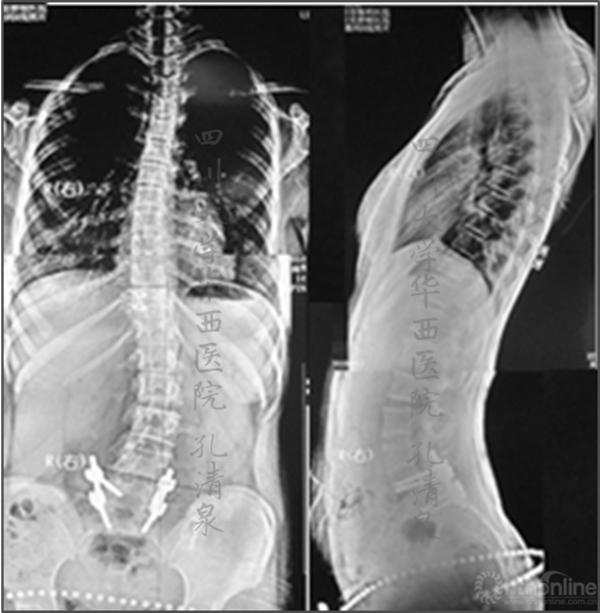

图1 术前X线示:腰5椎IV度滑脱并脊柱侧凸,颈胸弯中立位16°,减轻位0°,胸弯中立位50°,减轻位12°,腰弯33°,减轻位5°,均为非结构性弯。

图2 侧弯的左右bending位摄片及腰骶部CT的矢状面重建及表面重建